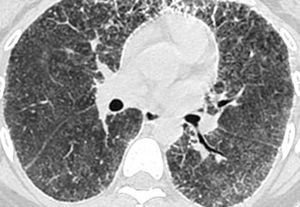

Las imágenes demostraron la presencia de puntiformes y difusas calcificaciones bilaterales, de predominio subpleural, en pleura mediastínica y en los septos interlobulillares. Los segmentos posteriores e inferiores estaban mayoritariamente afectos (fig. 2). También se visualizaron nódulos calcificados a nivel de segmentos anteriores (fig. 2B). El estudio detallado de alta resolución demostró un "patrón en empedrado" o crazzy-paving con marcado engrosamiento de los septos interlobulillares asociado a áreas parcheadas de aumento de la densidad en "vidrio deslustrado" o ground-glass, con mayor afectación de los segmentos posterobasales (figs. 3A y B). A nivel de los lóbulos superiores también se evidencian pequeños quistes subpleurales (fig. 3C).

Fig. 3. Las imágenes tomográficas de alta resolución demuestran la presencia de áreas mal definidas de aumento de densidad en vidrio deslustrado o ground-glass, con moderado engrosamiento de los septos interlobulillares, principalmente en los segmentos anteriores, adoptando en conjunto un "patrón en empedrado" o crazy-paving pattern (A). Secciones inferiores (B) demuestran la mayor afectación de las bases pulmonares. (C) También pueden visualizarse pequeños quistes subpleurales (flechas).